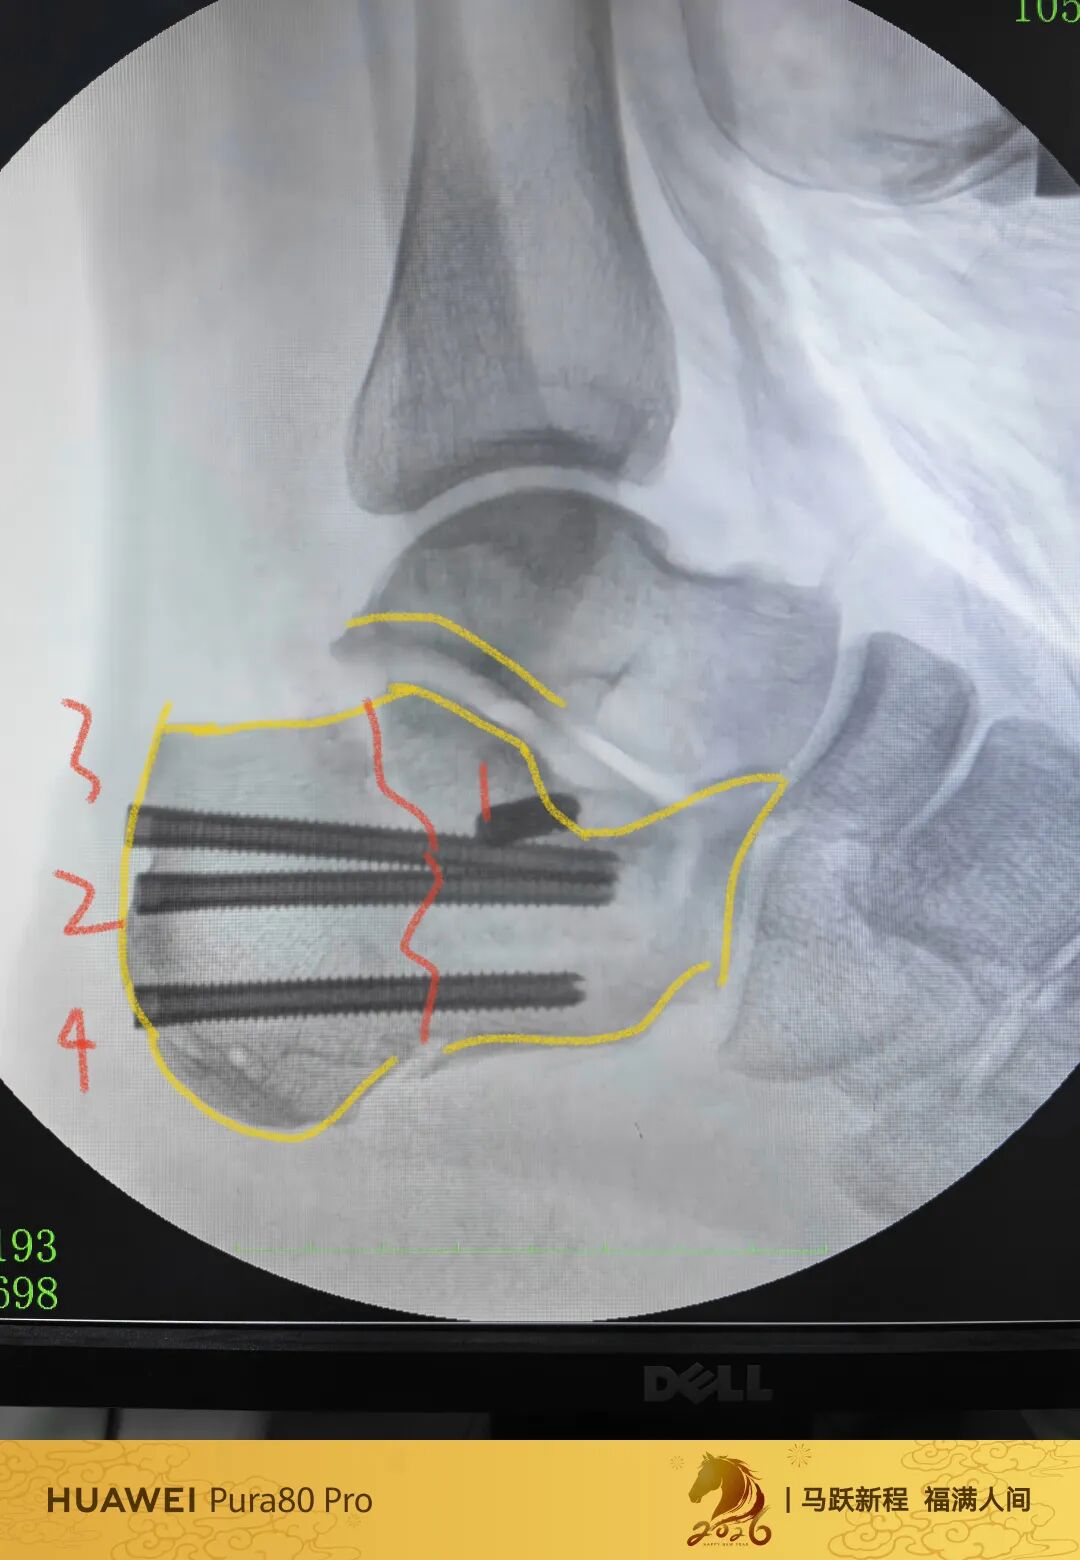

第60例跟骨微创了,虽然已经彻底放手,尽量只动嘴,但还是有小问题小瑕疵,无法完全避免。